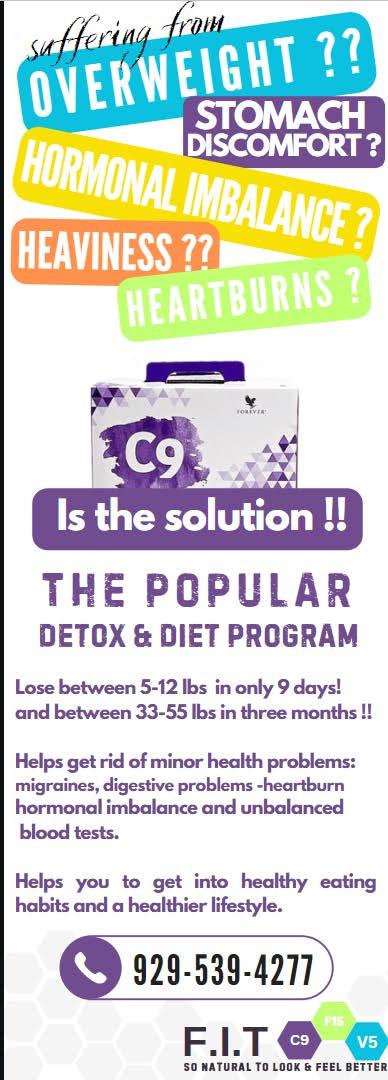

KOSHERSKINNYSHOT TM FAST ACTION WEIGHTLOSS INJECTIONS. 100% PURE INGREDIENTS TREATMENTS AVAILABLE: OZEMPIC - MOUNJARO - TRULICITY - WEGOVY - SEMAGLUTIDE - TIRZEPATIDE STARTING AT $249/MONTH 718.719.1282 THINWELLNESSCLUB.COM Chaim?!? Is that you? Having lost 50 lb. over the winter, my country folks don’t recognize me. With kosher skinny shots you can look great and feel great in record time. Sign up and expect the compliments.